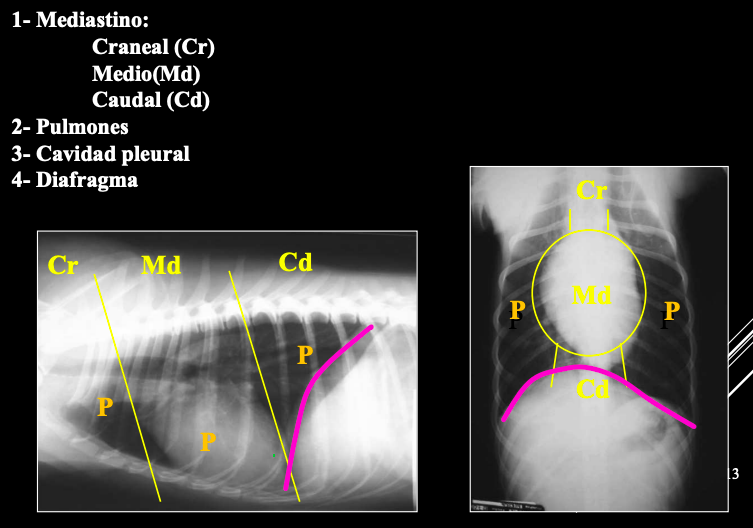

ESTRUCTURAS INTRATORÁCICAS

- Mediastino

- Pulmones

- Cavidad pleural

- Diafragma

El mediastino es el espacio medio de la caja torácica, situado entre las pleuras mediastínicas. Importante

PARTES DEL MEDIASTINO

- Craneal (Cr): Nervios, nodulos linfaticos, vasos (Arteria subclavia izquierda, tronco braquicefalico, vena cava craneal, vena acigos...)

- Medio (Md)

- Caudal (Cd)

Órganos mediastínicos visibles:

- Esófago (a veces), timo (jóvenes), tráquea, corazón, aorta, VCC.

Órganos no visibles:

- Vasos (A. subclavia izda., tronco braquiocefálico, V. cava craneal, V. ácigos).

- Nervios.

- Nódulos linfáticos.